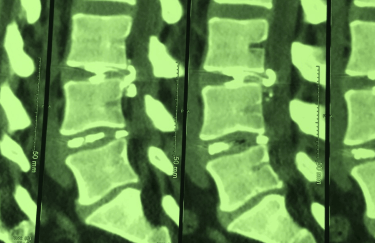

Symptoms: Severe disabling low back and sciatica pain for two years

Discogel in the CT Scan

An intriguing case involved severe herniation and disc rupture between L4 and L5 vertebrae, causing intense pain. Opting out of surgery, the patient chose to try Discogel. Due to severe foraminal stenosis from the extruded disc, the Discogel injection was cautiously prolonged to one hour. Post-injection CT scan revealed effective penetration into fragmented disc components in the narrowed foraminal space.

The patient's pain gradually diminished after 4-5 weeks, and complete relief was achieved after several months.

The first image is six months post-injection, and the second image is three years post-injection."